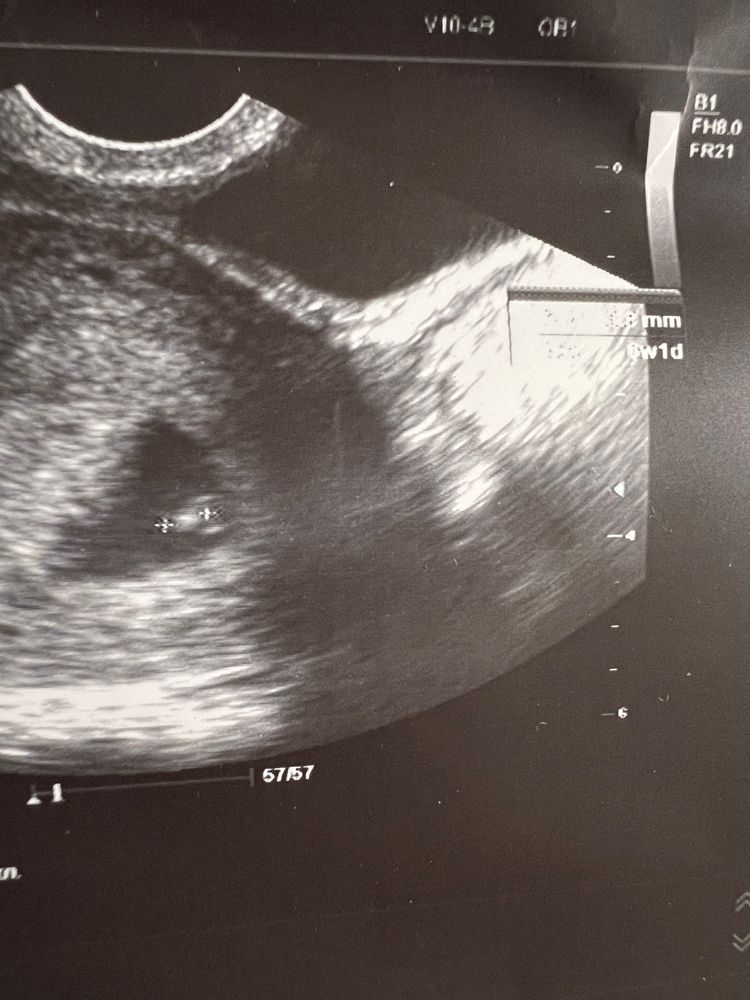

24 дпп - малыш на месте, сб + 💓

по узи 6нед1д, по месячным сегодня 6нед ровно и 24 дпп моей крио-пятидневочки 🥹

ктр 3.7 мм, сб 93 🥰